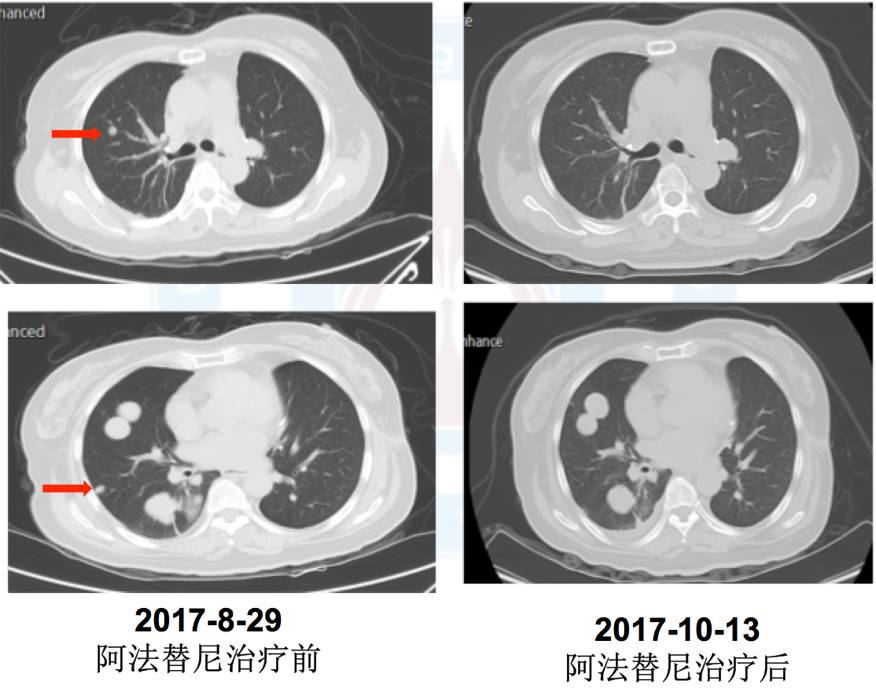

5.五线:2017年9月5日阿法替尼40mg靶向治疗,治疗1周出现I度皮疹、消化道反应,治疗45天疗效评价PD(混合疗效,部分缩小)。

肺内科李安娜医生:该患者是接受EGFR TKI治疗耐药后出现2种混合癌病理类型,这个混合癌病理类型目前考虑是肿瘤异质性引起,而不是腺癌的转化。因为最初手术切除2个肺结节病理提示是2种单纯癌组织成分,而不是混合癌成分。患者在二次肺结节穿刺活检病理提示肉瘤样癌,但给予阿法替尼治疗后部分肿瘤组织缩小,考虑缩小肿瘤组织成分为腺癌。目前患者已经是5线治疗,PS评分2分,但疼痛症状加重。既往治疗中3线治疗后,阿法替尼治疗时可以观察到部分有效。针对下一步治疗目前组内讨论意见是:因为该患者为混合性腺癌,同时存在EGFR突变,且既往阿法替尼治疗可观察到部分有效,毒副反应为轻度I度,目前已到6线治疗,无标准治疗方案,可以考虑靶向治疗联合化疗;病理为腺癌合并肉瘤样癌,可以选择泰素联合阿法替尼,间插治疗。

吴一龙医生:根据大家的讨论,针对该患者下一步的治疗建议:考虑患者阿法替尼治疗后部分病灶有缩小,且患者由长期卧床到现在可以坐轮椅,生活质量有改善,因此建议继续阿法替尼治疗。陆舜教授曾经报告过多靶点抗血管生成抑制剂呋喹替尼联合EGFR-TKI治疗NSCLC是有一定效果的,我们可考虑加入抗血管生成小分子TKI。